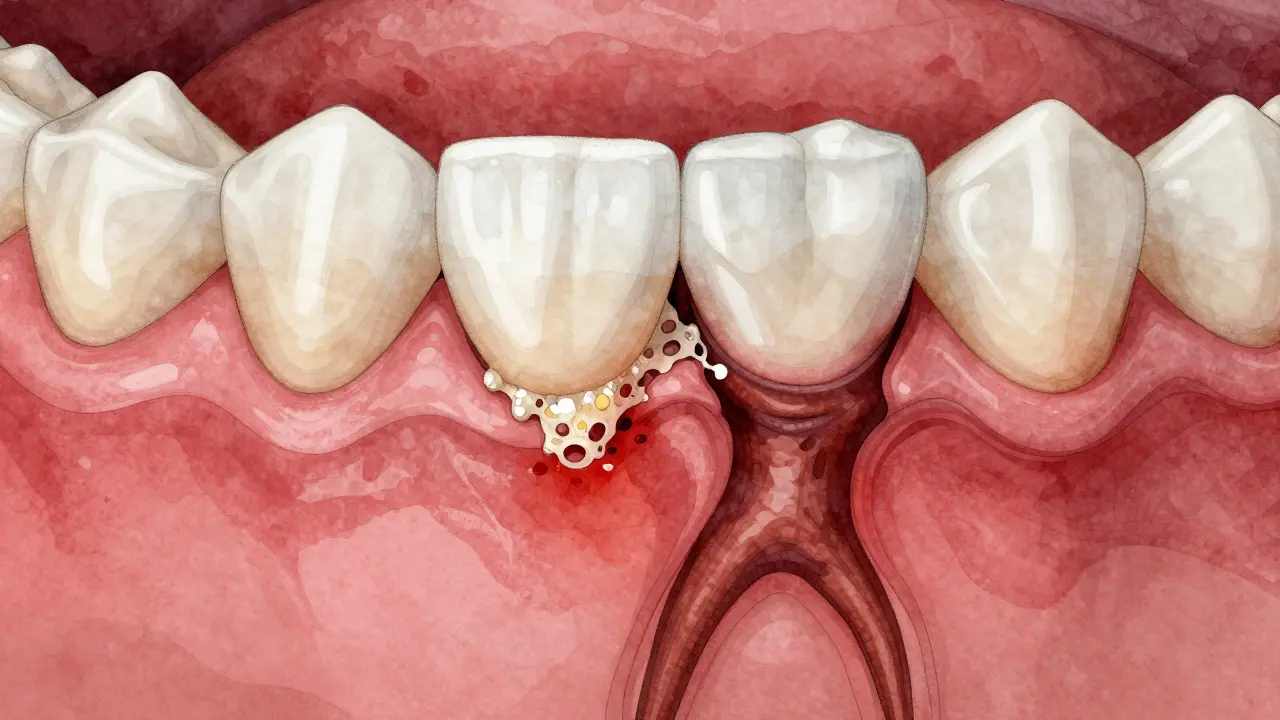

Průřez ústní dutiny ukazující infekci pod korunkou a šíření bakterií do kosti.

Co se stane, když zánět ignorujete?

Zánět v puse není jen „nepříjemnost“. Je to infekce, která se šíří.

• Do kosti - zánět z dásní se může dostat k kořeni a zničit kost, která drží zub. To se jmenuje periodontitida. A ta je nevratná.

• Do abscesu - hnis se hromadí a vytváří kapsli. Může se vyprázdnit, ale zpět se vrátí. Nebo se rozšíří do obličeje.

• Do krku a krve - bakterie z úst se mohou dostat do krevního oběhu. U lidí s oslabeným imunitním systémem to může vést k infekcím srdce (endokarditida) nebo plic.

• Ztráta zubu - pokud se kost kolem zubu zhroutí, zub se vypne. A e-max korunka s ním spolu zmizí.